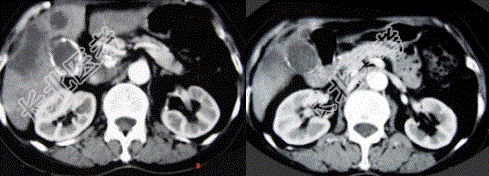

- 单项选择题女性,66岁。右上腹痛, 发热伴有黄疸2个月余,消瘦、纳差, 影像表现如图所示,最可能的诊断是

A、胆囊结石及脂肪肝

B、胆囊结石及肝血管瘤

C、胆囊癌肝转移

D、肝内胆管细胞癌

E、胆囊癌及原发性肝癌